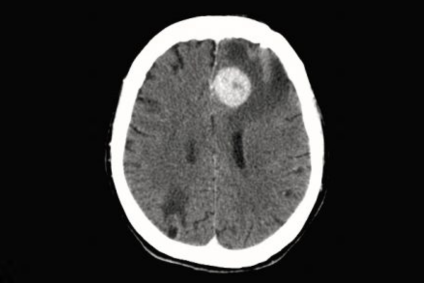

Con una presentación clínica variable, incluye déficits neurológicos focales, alteraciones cognitivas, cambios en el comportamiento y, en algunos casos, síntomas de hipertensión intracraneal como náuseas y vómitos. En consiguiente, su diagnóstico requiere un alto grado de sospecha clínica y el uso de herramientas avanzadas como la resonancia magnética (functional magnetic resonance imaging, fMRI, en inglés). Siguiendo esta línea, las principales características del linfoma cerebral son las siguientes:

- Diagnóstico por imagen: Lesiones homogéneamente realzadas con contraste y edema leve.

Como ya adelantamos previamente, el linfoma cerebral se diagnostica mediante resonancia magnética con gadolinio y, en casos específicos, análisis de líquido cefalorraquídeo para detectar células malignas. Su tratamiento se basa en quimioterapia de altas dosis con metotrexato, complementada con radioterapia o trasplante autólogo de células madre, aunque las recaídas son frecuentes.